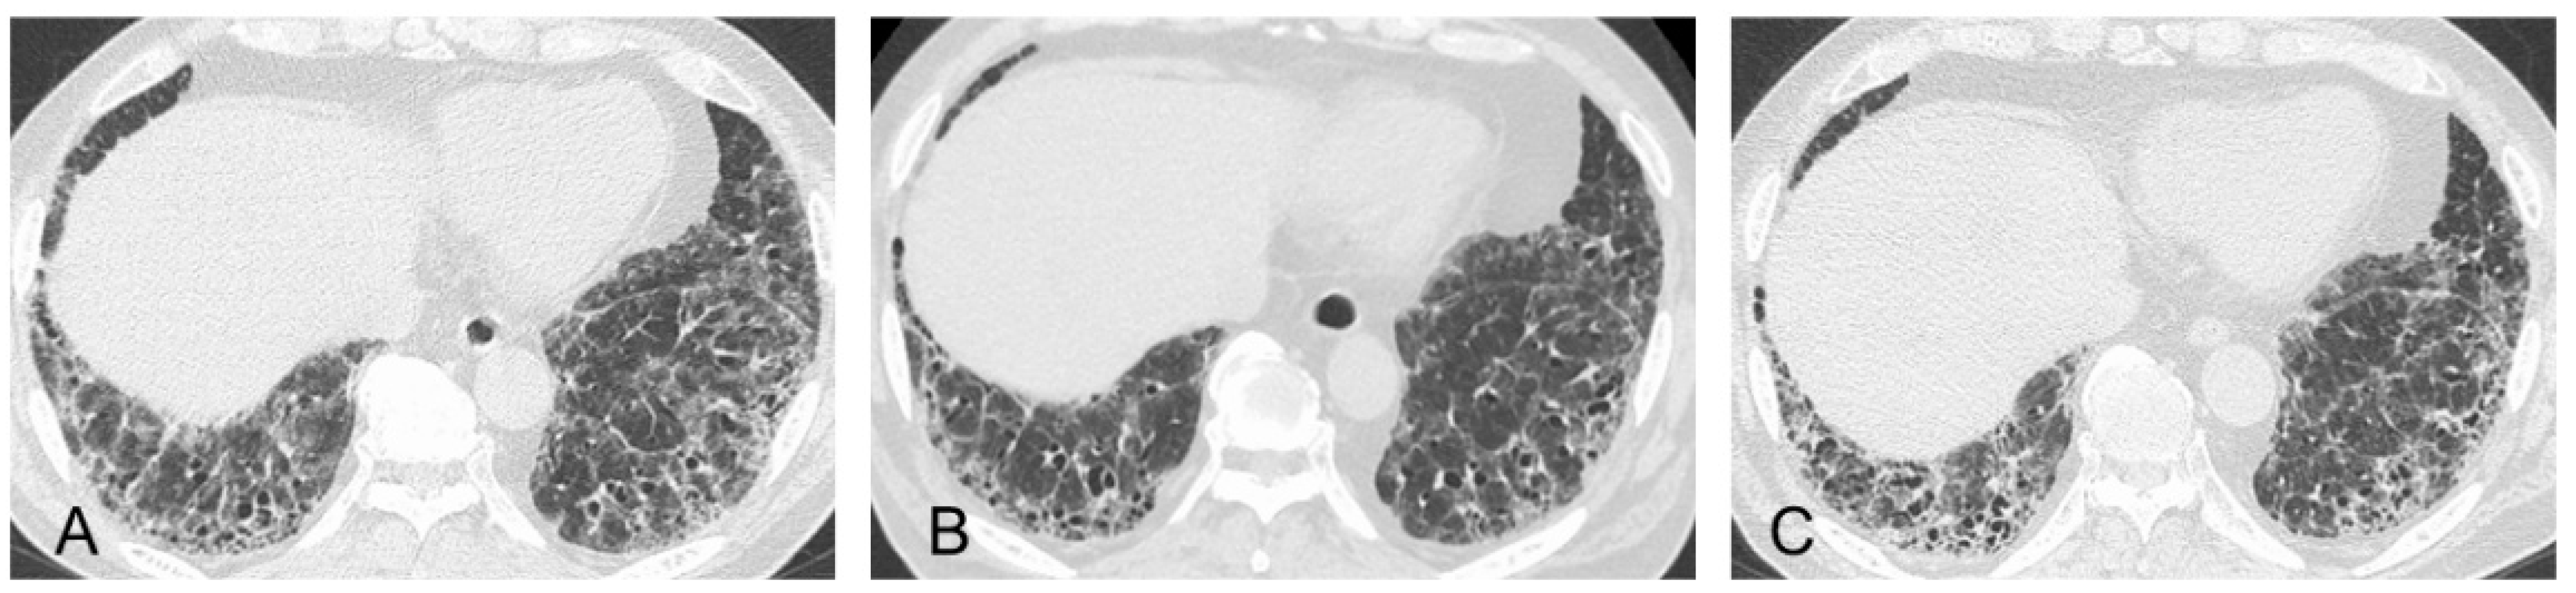

In contrast, the factors favoring fibrotic change are nonincreasing levels of CRP or ESR, a decrease or leveling off of the MPO-ANCA titer, expansion of fibrotic change as reticulation with traction bronchiectasis and honeycombing on HRCT without increasing attenuation (i.e., ground-glass opacity [GGO] and consolidation), and pathologically patchy fibrosis as a UIP pattern and/or fibroblastic foci in a lung specimen without prominent inflammatory cells [1,2,3,30,31,33,34,47,48,49,50]. As a caveat, GGO, which is a finding typically associated with inflammation or infiltration, does not always represent reversible lung disease, but rather in some cases, it may represent microscopic fibrosis [51]. Therefore, lung biopsy may be useful to assess whether inflammatory or fibrotic change is dominant [36,49,52]. Importantly, recent reports have shown that all etiologies associated with ILD can lead to a poor prognosis, particularly in cases in which a component of UIP is found to a certain degree [53,54,55]. In other words, some cases represent the natural evolution of the inflammatory change of ILD into fibrotic change [56]. Adegunsoye et al. noted that honeycombing represents a progressive fibrotic ILD phenotype regardless of underlying conditions such as connective tissue disease, idiopathic ILD, or fibrotic hypersensitive pneumonia [57]. In addition, AE of ILD can affect all patients with ILD but apparently occurs more frequently in patients with an underlying UIP pattern, which is a most harmful event and can be a major cause of death [58,59]. Therefore, the presence and/or expansion of fibrotic change particularly in the UIP pattern appearing as reticulation with traction bronchiectasis and honeycombing during follow-up has an important prognostic implication in all etiologies associated with ILD [36,40,53]. If we determine that fibrotic change is dominant, we consider starting an anti-fibrotic therapy such as nintedanib or pirfenidone, which has been approved for the treatment of IPF [60,61,62]. The INBUILD study showed the effectiveness of nintedanib on PF-ILD other than IPF, and nintedanib might have the potential to suppress the AE of ILD [63]. Post hoc analysis of the INBUILD study suggested a treatment benefit of nintedanib across all subgroups of patients with PF-ILD, including autoimmune ILD, although the trial was not powered to provide evidence to address this specific question [64]. In the RELIEF study, although the quality of evidence was rated as low, pirfenidone also significantly suppressed the deterioration of forced vital capacity in patients with progressive fibrotic ILD due to four diagnoses: connective tissue disease-associated ILDs, fibrotic NSIP, fibrotic hypersensitivity pneumonitis, and asbestos-induced lung fibrosis [65]. Taken together, expanding fibrotic change in patients with a UIP pattern can lead to the high risk of PF-ILD and AE of ILD, which means a poorer prognosis even in those with MPO-ANCA-positive ILD. Therefore, starting anti-fibrotic therapy such as nintedanib should be considered in such a case (Figure 5, same patient as in Figure 2).

Figure 5.

Radiologic course of the same patient with MPO-ANCA-positive ILD shown in Figure 2. (A) At the time of transbronchial lung cryobiopsy, high-resolution computed tomographic (HRCT) imaging showed subpleural reticulations with traction bronchiectasis as the framework of UIP and ground-glass opacities (GGOs) to some extent in the bilateral lung field. (B) At six months after anti-inflammatory treatments, the findings regarding GGOs were improved. (C) At six more months later, HRCT showed a moderate increase in disease extent of the reticulations and traction bronchiectasis as indications of progressive fibrosis, for which therapy with the anti-fibrotic agent nintedanib was initiated.